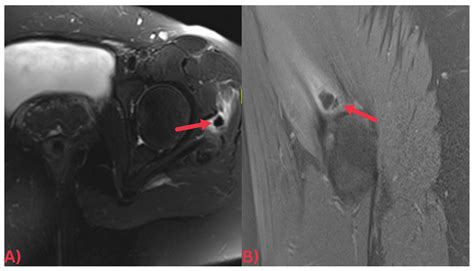

• Imaging Studies: X-rays, ultrasound, and magnetic resonance imaging (MRI) can help identify the presence of hydroxyapatite crystals and assess the extent of the deposits.

Imaging studies are particularly important in diagnosing HADD. X-rays can show calcifications in the affected areas, while ultrasound and MRI provide more detailed images of the soft tissues and joints. Laboratory tests can help rule out other conditions that may cause similar symptoms.